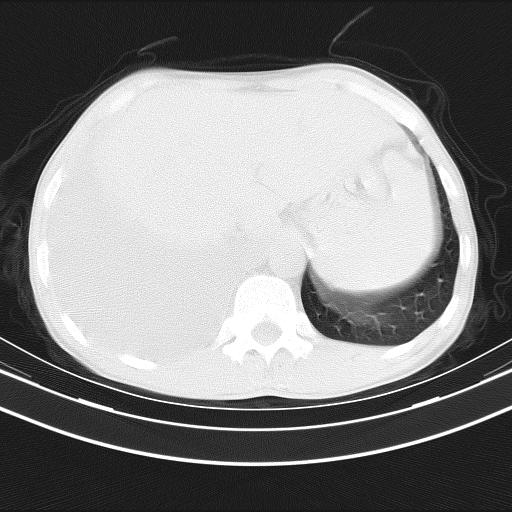

男性,44岁,结核病史多年。现胸闷气短,咳嗽,偶咳血。

右侧胸腔积液

右肺下叶不张

双肺多发结节影最分空洞形成考虑占位不除外结核

双肺陈旧性病变

1、右侧大量胸腔积液伴右肺压缩性膨胀不全,建议抽液治疗后复查 2、两肺继发性tb伴空洞形成。

1)两肺继发性肺结核伴空洞形成,左肺多发性结核球。2)右侧大量胸腔积液伴右肺部分膨胀不全。3)纵隔淋巴结肿大。

吉大一院胸水抽检结果:结核性胸水